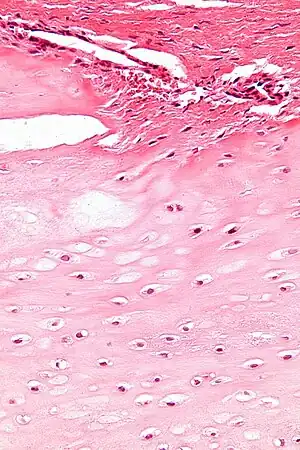

| Enchondromas are present in Maffucci syndrome | |

Maffucci syndrome is a very rare disorder in which multiple benign tumors of cartilage develop within the bones (such tumors are known as enchondromas).[1] The tumors most commonly appear in the bones of the hands, feet, and limbs, causing bone deformities and short limbs.[1]